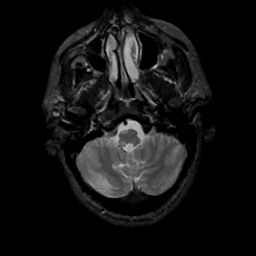

MR Study #15, June 9, 1991 -- Slice #8

[Home][Help][Clinical][Tour 1][Tour 2] Slice 8